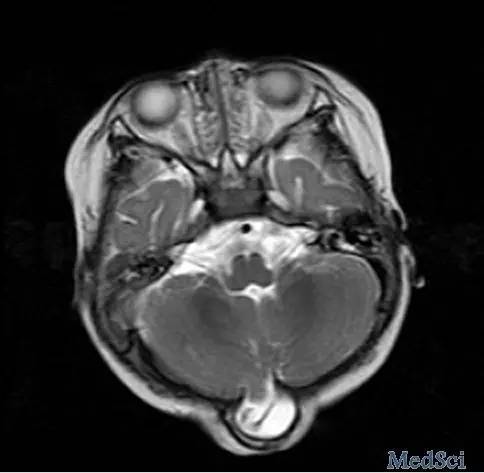

1岁患儿因枕部出现囊样突起而就诊于神经外科诊所,此囊样突起自患儿出生一直维持到现在。患儿为足月剖腹产,并没有出现神经系统症状,囊样突起自出生以来也没有继续增长。体格检查发现患儿的头围正常。囊样突起的大小为2.5 × 2.5 cm,易哭闹。系统检查并未发现相关的异常。头部磁共振成像结果如下(图1⇓)。

讨论:MRI显示患儿枕骨局部缺损,脑脊液充满的囊腔加上部分脑组织从缺损部位向外膨出形成疝,表明患儿存在脑膨出问题(图 2⇓)。